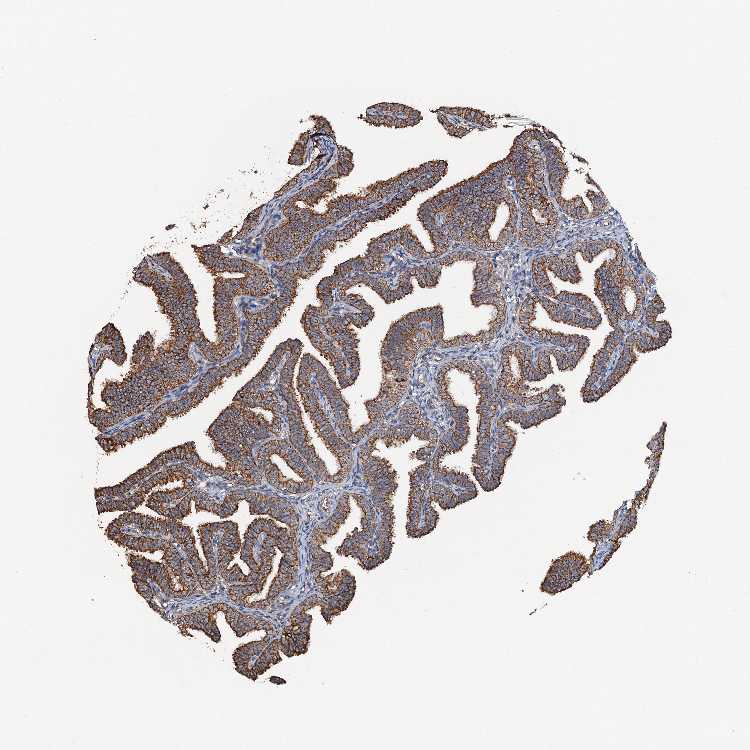

FALLOPIAN TUBE - Antibody stainingi

Antibody staining in the annotated cell types in the current human tissue is reported as not detected, low, medium, or high, based on conventional immunohistochemistry profiling in selected tissues. This score is based on the combination of the staining intensity and fraction of stained cells.

Each image is clickable and will lead to virtual microscopy that enables deeper exploration of all samples and also displays staining intensity scores, fraction scores and subcellular localization as well as patient and tissue information for each sample.

Antibody HPA039371Antibody HPA040174

Ciliated cells (cell body) -High

Ciliated cells (cilia axoneme) -Not detected

Ciliated cells (ciliary rootlets) -Not detected

Ciliated cells (tip of cilia) -Medium

Glandular cells High-

Non-ciliated cells -High